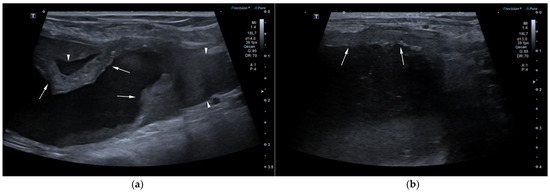

AUS in all three dogs revealed a fluid-filled cavitary structure originating in the caudal peritoneum between the colon and urinary bladder and extending cranially through the mid-abdomen, causing a mass effect. In cases 1 and 2, the lesion continued bilaterally as paired, thin tubular extensions coursing caudally through the inguinal rings adjacent to each testis (Figure 1a). In case 1, a focal mural narrowing resembling a uterine cervix was noted caudally (Figure 1b). The wall was thin and smooth in case 1, while in case 2 it was irregular, especially in its caudal aspect (Figure 2a,b). No information was available regarding the course of the UM horns or wall appearance for case 3. The luminal content consisted of echogenic, inhomogeneous fluid in all cases (Figure 3a); in case 2, sedimentation created fluid–fluid levels (Figure 3b).

Additional findings in all dogs included: enlarged, heterogeneous, cystic prostate; echogenic sediment in the urinary bladder; free peritoneal fluid [moderate and echogenic in case 2 (Figure 2a); mild and anechoic in cases 1 and 3]; and bilateral medial iliac lymphadenomegaly (moderate in cases 2 and 3; mild in case 1).

Figure 2. AUS of case 2: (a) Longitudinal view of the caudal UM, showing irregular wall margins (arrows), intraluminal inhomogeneous fluid, and free echogenic peritoneal fluid (arrowheads); (b) Detailed view of the UM wall demonstrating luminal irregular margins (arrows).